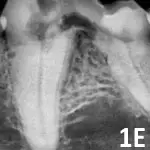

A dental radiograph shows the roots of a canine tooth, highlighting the surrounding bone structure and any potential periodontal disease. The image reveals the clarity of the root canal and the condition of the alveolar bone.

Figure 1E

Mandibular first molar affected by stage 4B tooth resorption.

Stage 4: Extensive hard tissue loss. Most of the tooth loses integrity. In stage 4A (See Figure 1D), the crown and root are equally affected; in stage 4B (See Figure 1E), the crown is more severely affected than the root; in stage 4C (See Figure 1F), the root is more severely affected than the crown.